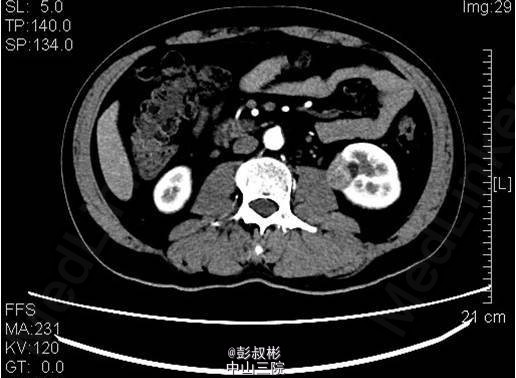

3、既往病史:高血压,高尿酸,高血脂6年,2013年行“右输尿管结石碎石取石术” 4、入院查体:未见明显异常体征。 5、影像学检查:中下腹部CT平扫+增强+CTU:左肾中盏可见结节状高密度影,直径约为6mm,基本同前。左肾下部可见大小约为36×21×23mm稍高密度影突出于包膜生长,较前明显增大,凸向肾外生长,浅分叶,其内见脂肪密度影,增强扫描可见轻度强化,病灶与左侧腰大肌关系密切。